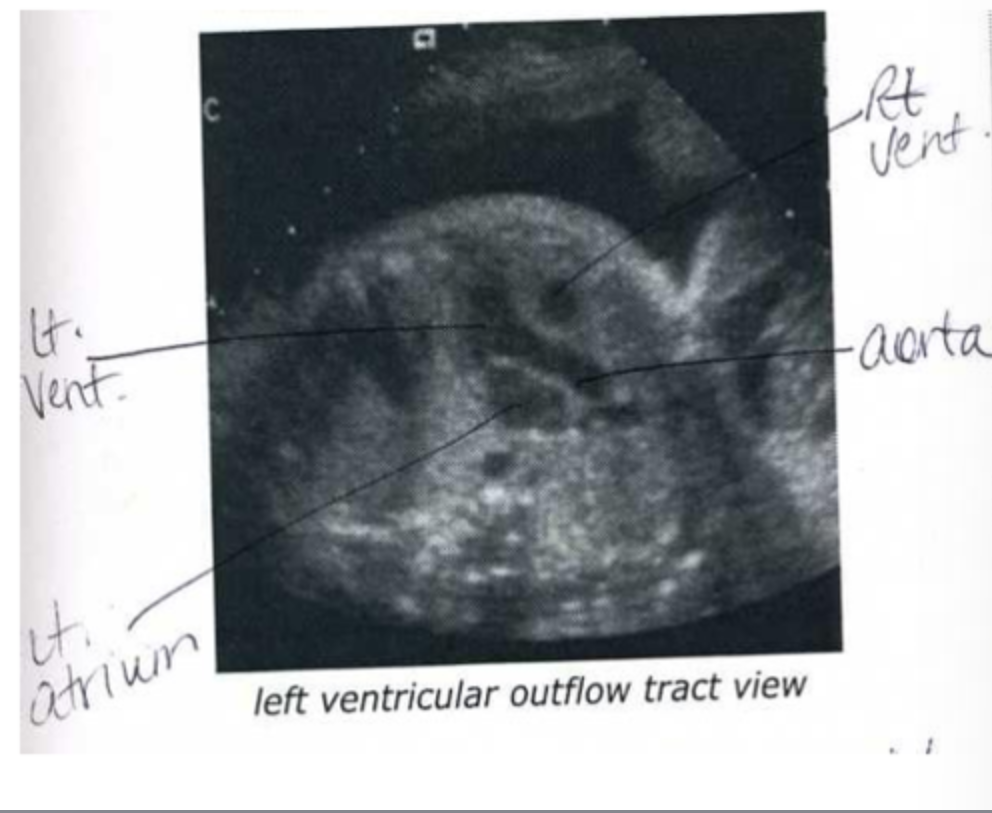

What is LVOT?

connects left ventricle to aorta